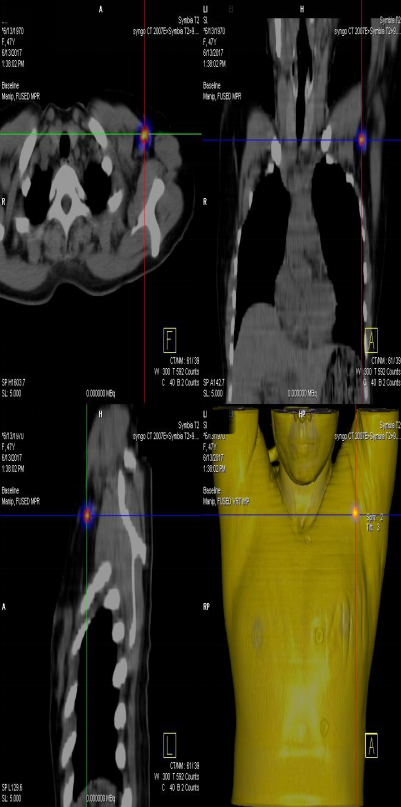

前哨淋巴結(jié)顯像技術(shù)一般在腫瘤附近注射放射性核素標(biāo)記特殊藥物,這種藥物會被前哨淋巴結(jié)攝取,存在于前哨淋巴結(jié)中。24小時之內(nèi)都可用SPECT-CT進行前哨淋巴結(jié)顯像檢查。

找到幾個淋巴結(jié)沒有明確的限制,淋巴結(jié)核素計數(shù)小于第一個SLN計數(shù)的10%就不再是前哨淋巴結(jié)了。

患者李女士,發(fā)現(xiàn)右側(cè)乳腺腫物,來我院就診,行乳腺腫物局部擴大切除術(shù),術(shù)后病理回報:右乳腺浸潤性導(dǎo)管癌III級,伴原位癌。擬行右乳腺癌切除術(shù),提檢前哨淋巴結(jié)顯像檢查,明確有無淋巴結(jié)轉(zhuǎn)移。